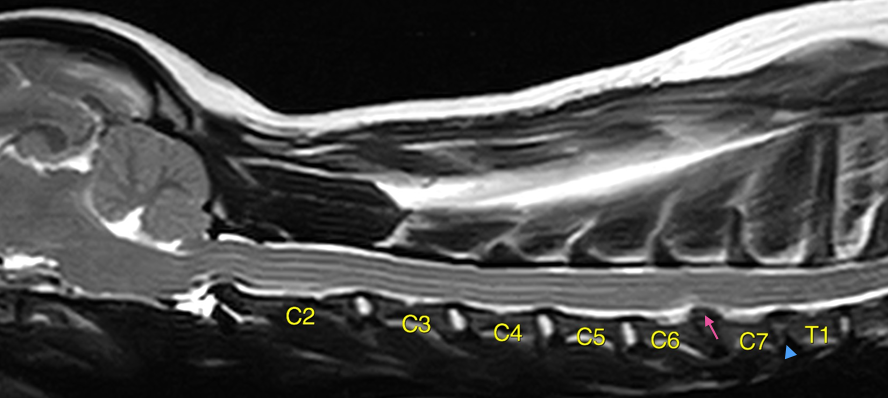

これらは問診・身体検査・神経学的検査などを踏まえ、最終的にはMRI検査によって画像診断します(図2)。

図2 頚部MRI(T2強調画像) 変性した椎間板は白さが無くなる(青矢頭)、椎間板物質が脊柱管内に突出して脊髄を圧迫した状態が椎間板ヘルニア(ピンク矢印)